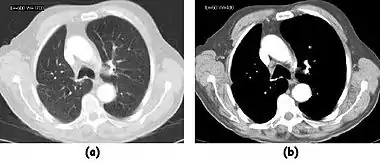

![]() Fig. 7.15.2: Effect of window width and level on CT image display: (a) Level = 50; Width = 200. (b) Level = 50; Width = 400. The image in (a) is displayed with greater contrast and appears noisier than that in (b). | ![]() Fig. 7.15.3: Effect of window width and level: (a) Level = -600; Width = 1700. (b) Level = -60; Width = 400. Image (a) displays the lung tissue more clearly, while image (b) can be used to highlight any pulmonary lesions. |

- Examples of image display manipulation are shown in the two figures above. In Figure 7.15.2, the same image of a slice through a patient's liver is displayed using a relatively narrow window (high contrast) and also with a wide window. The image with the narrower window appears noisier, but this is merely a reflection of the fact that the gray scale is spread over a narrow range of CT-numbers.

- Figure 7.15.3 illustrates the use of a relatively narrow window to highlight pathology in the lungs.